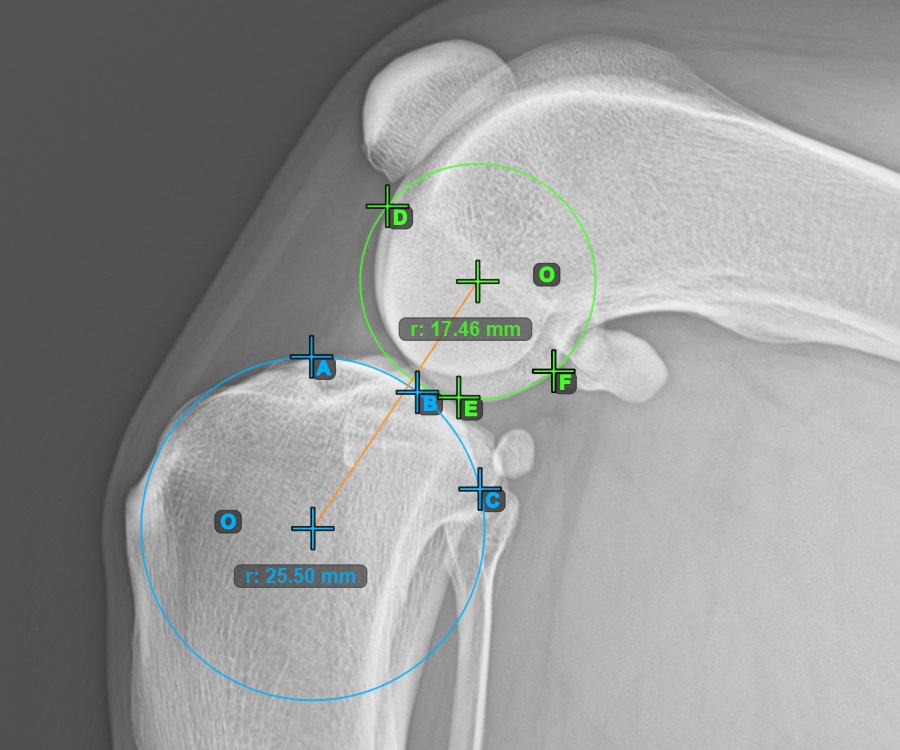

Continue by marking the three points on the articular surface of the Condylus Femoris.

Mark the three points on the main condylus of the femoral bone (Condylus Femoris). Regardless of the order, make sure to mark the most cranial point, the most caudal point and the midpoint of the Condylus Femoris. A circle will be automatically constructed based on the three placed points.

The image below represents a typical placement of the three points on the Condylus Femoris.